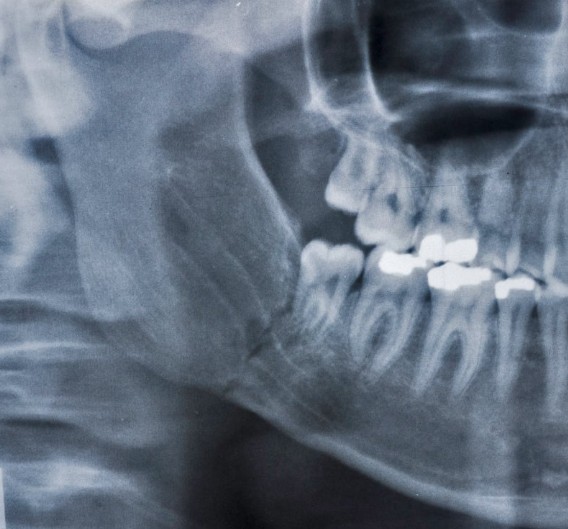

Estudios de imagen: radiografías y tomografía (CBCT)

Las radiografías panorámicas nos dan una visión general del estado de los huesos y los dientes, pero cuando necesitamos ver con más detalle, usamos la tomografía computarizada (CBCT). Esta tecnología nos permite ver en 3D cuánto hueso hay, en qué calidad está y si hay zonas donde necesitamos hacer regeneración. Es una herramienta clave para planificar tratamientos con injertos o implantes de forma segura y personalizada.

El diagnóstico suele incluir una radiografía panorámica y, si necesitamos más precisión, una tomografía 3D (CBCT). Esta última es clave porque nos permite medir el volumen de hueso disponible, identificar zonas debilitadas y planificar procedimientos como injertos, regeneración ósea o implantes. La tomografía también ayuda a detectar infecciones ocultas, quistes o pérdida ósea en áreas que no son visibles en una radiografía tradicional.